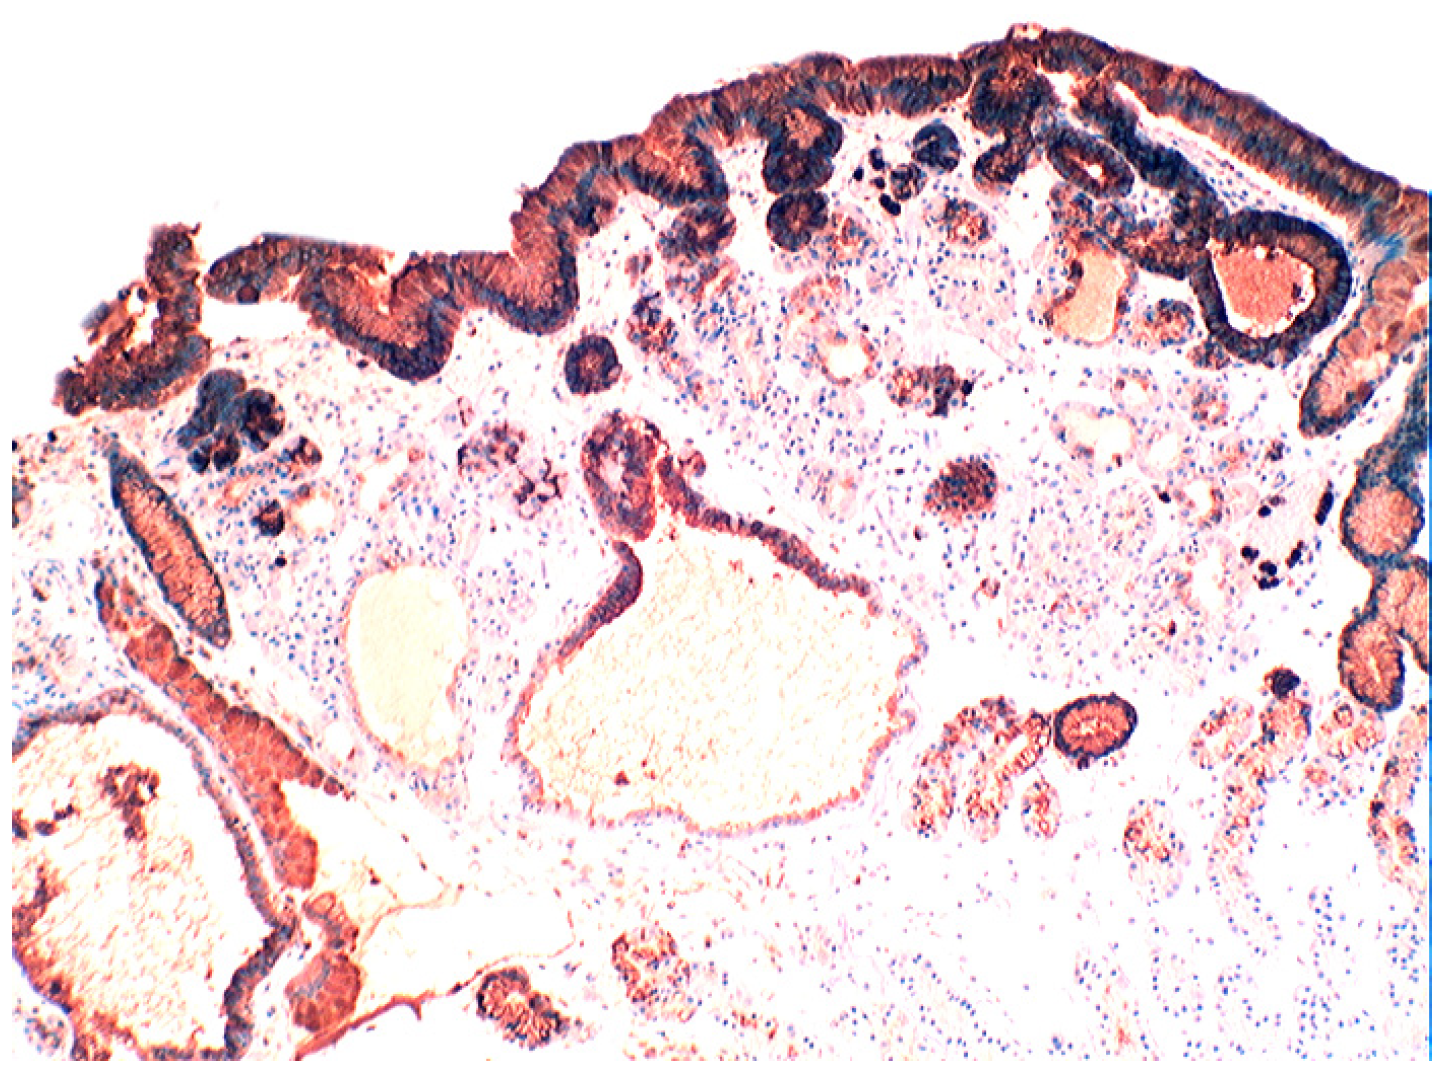

Increased lysozyme immunoreactivity was found In Barrett’s oesophagus; in the surface columnar epithelium, in the columnar epithelium of the pits of the glands (Figure 1), in goblet cells (Figure 2), as well as in Paneth cells in cases with intestinal metaplasia [24].

Barrett’s mucosa (pyloric phenotype) showing lysozyme expression in surface epithelium, foveolar epithelium, and pyloric glands (lysozyme immunostain, ×4).